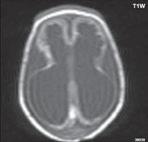

Obr. I.1.8a Dandy-Walkerova malformace, rozšířená IV komora (tvar klíčové dírky)

Obr. I.1.8b Dandy-Walkerova malformace, rozšířená IV komora široce komunikující s cisterna magna, hypotrofie mozečku (snímky zapůjčeny z archivu prim doc MUDr M Mechla, Ph D, MBA)

Obr. I.1.8c Dandy-Walkerova malformace, rozšířená IV komora široce komunikující s cisterna magna, hypotrofie mozečku (snímky zapůjčeny z archivu prim doc MUDr M Mechla, Ph D, MBA); stejný pacient jako na obr I 1 8b

Obr. I.1.8d Dandy-Walkerova malformace, rozšířená IV komora široce komunikující s cisterna magna, hypotrofie mozečku, vysoký úpon tentoria (šipka) (snímky zapůjčeny z archivu prim doc MUDr M Mechla, Ph D, MBA); stejný pacient jako na obr I 1 8b, c

Obr. I.1.8e Dandy-Walkerovo spektrum (hypoplazie vermis, IV komora je rozšířená a široce zeje) (snímky zapůjčeny z archivu as MUDr J Lisého, CSc )

Obr. I.1.8f Dandy-Walkerovo spektrum (hypoplazie vermis, IV komora je rozšířená a široce zeje) (snímky zapůjčeny z archivu as MUDr J Lisého, CSc ); stejný pacient jako na obr I 1 8e

Obr. I.1.8g Dandy-Walkerovo spektrum (hypoplazie vermis, IV komora je rozšířená a široce zeje), (snímky zapůjčeny z archivu as MUDr J Lisého, CSc ); stejný pacient jako na obr I 1 8e, f

D-W malformace je charakterizována hypoplazií vermis mozečku, rozšířením IV. mozkové komory, která se často cysticky vyklenuje dorzálně a může imitovat arachnoidální cystu, rozšířením zadní jámy lební a vysokým úponem tentoria s confluens sinum nad lambdovým švem. Okcipitální kost může být vlivem tlakových změn remodelována, existují i případy s porušením její kontinuity a encefalokélou. Hydrocefalus pozorujeme v 80 %, častá je přítomnost dysgeneze corpus callosum, schizencefalie.

D-W variant byl vyčleněn pro případy, kdy všechny základní příznaky nemusí být plně vyjádřeny nebo může některý zcela chybět. Bývá přítomna hypoplazie mozečku, což je dominantní příznak, IV. komora je obvykle rozšířena, někdy pozorujeme, že tvarem připomíná na axiální řezu „klíčovou dírku“, zadní jáma lební naopak rozšířena nebývá.